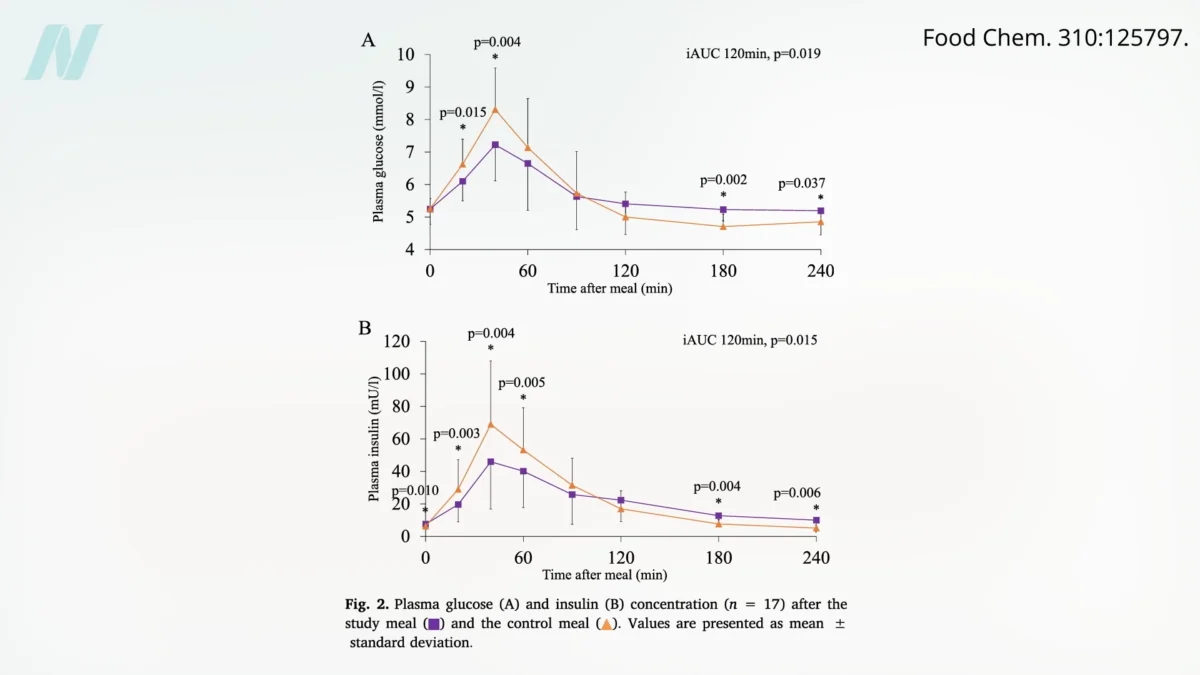

Onions: Unpacking the Evidence from Randomized Human Trials for Health Benefits

Onions, a staple in kitchens worldwide and a cornerstone of countless culinary traditions, have long been lauded for their potential health-promoting properties. While anecdotal evidence and traditional medicine have often…